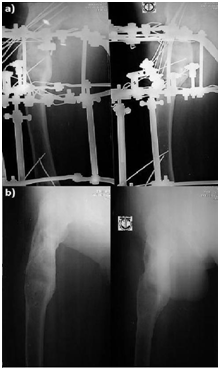

On further questioning, he was treated for a hip fracture 2 years back in another hospital, where a dynamic hip screw was inserted. He went through the standard post-operative rehabilitation and was back on his feet allowing some sport activities, although at a lower functional level. He has always experience persistent pain over the old injury and shortening of the leg. At 6 months prior to seeing us, he under gone another surgery for removal of the Dynamic Hip Screw due to worsening hip pain. After making a thorough assessment, the surgical plan was to fix the fracture by close reduction and external fixation by application of the Ilizarov apparatus (Figure 2).

Figure 2 Pathological fracture of the femur stabilised with Ilizarov apparatus.

The patient was placed supine on a traction table and femur was realigned by traction. Multiple Ilizarov wires were introduced through the femoral neck and the throcanteric region. These wires were held in position attached to a Russian femoral arch. The varus deformity was corrected at the fracture site by giving a valgus force on the Russian femoral arch and the fracture was stabilised by connecting it distally to two full rings at the shaft, tranfixed with intraosseos wires. Multipe console wires were introduced to the bone at strategic positions. The neck shaft angle was reduced to 130°. No osteotomy was done for this operation.

The patient was allowed partial weight bearing for the first 1 month and gradually progress to full weight bearing. At 3 months the patient was pain free on the Ilizarov frame, he demonstrated almost full range of movement of the hip and walk with less shortening. Radiograph at 6 months showed union at the fracture. At 10 months follow up, radiograph showed thickening of the cortex around the fibrous dysplasia lesion and increased bone density which replaced the cystic lesions (Figure 3). The frame was removed at 10 months post surgery.

Figure 3 Radiograph showed thickening of the cortex around the fibrous dysplasia lesion and increased bone density. a. At 10 months on Ilizarov apparatus. b. After removal of Ilizarov apparatus.